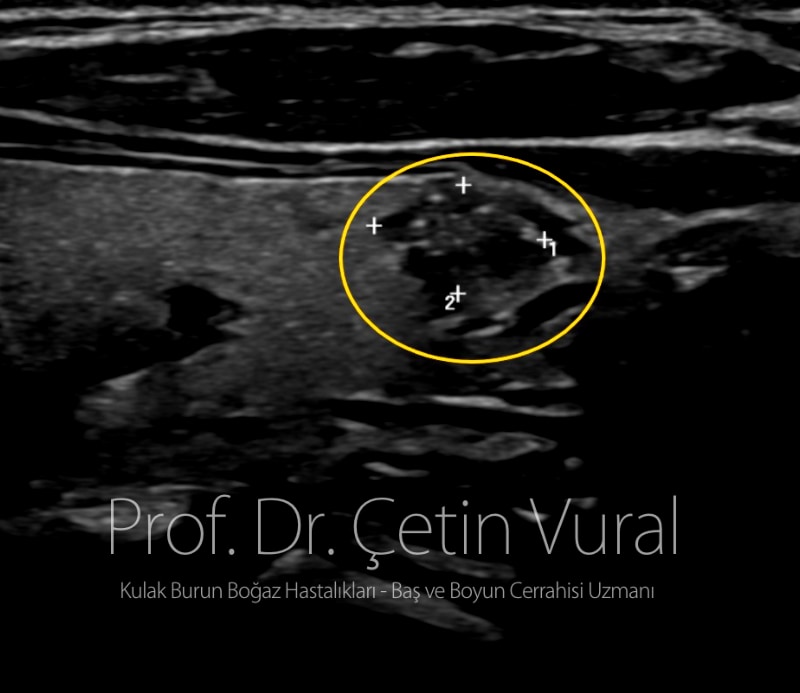

Kırk bir yaşında kadın hastanın rutin ultrason incelemesinde tiroid bezi sol yarısında kanser açısından şüpheli nodül saptanmıştı. Yapılan iğne biyopsisi yine papiller kanser açısından şüpheli olarak yorumlanınca hastanenin endokrin bölümü tarafından bize yönlendirildi.